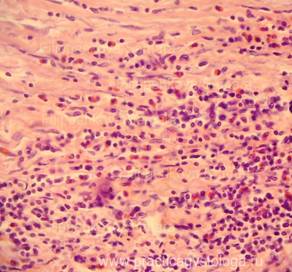

Рис. 1, 2. Картина очагового острого гнойного межуточного миокардита: очаговая и очагово-диффузная инфильтрация стромы миокарда сегментоядерными нейтрофильными лейкоцитами в различной степени выраженности, лейкоциты как чётко контурирующиеся, так и в состоянии распада. Отдельные кардиомиоциты и мелкие их пучки в состоянии некроза. Окраска: гематоксилин-эозин. Увеличение х100, х250.